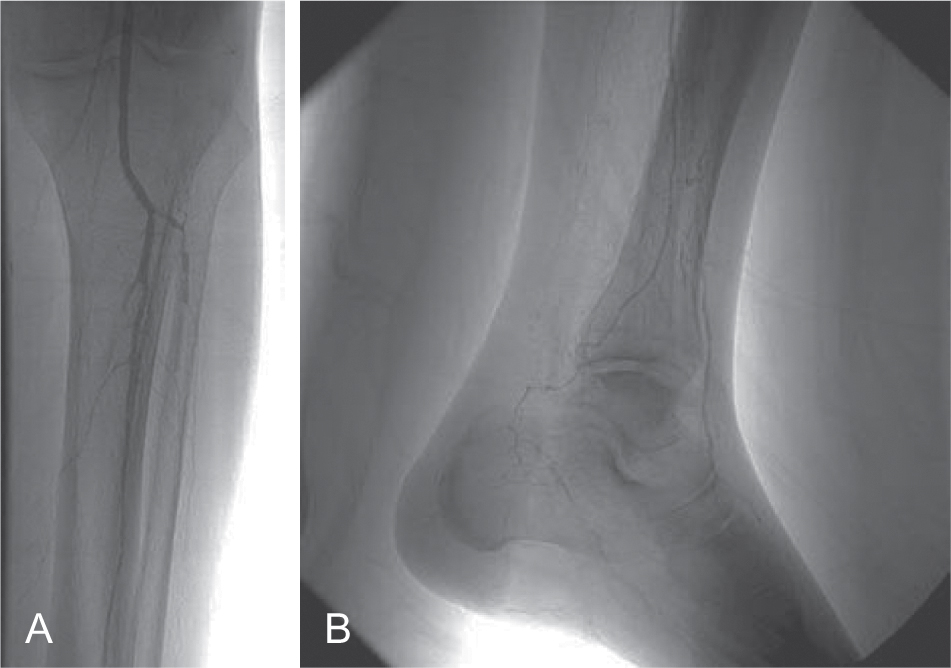

Bệnh động mạch ngoại biên (PAD) là một bệnh của quá trình lão hóa với tỷ lệ hiện mắc là 10% ở người trên 65 tuổi và 30% ở người ở độ tuổi 80, biểu hiện bằng chứng đau cách hồi hoặc các triệu chứng thiếu máu chi nguy kịch. Các triệu chứng thường xuất hiện ở phần xa so với mức độ hẹp. Nếu bệnh nhân hoạt động, đau cách hồi là triệu chứng điển hình; nếu bệnh nhân không hoạt động, PAD có thể biểu hiện bằng đau khi nghỉ, loét, đỏ da khi hạ thấp chi, hoặc hoại tử (Hình 25.1). Khi chứng đau cách hồi tăng đột ngột, phải xem xét đến huyết khối tại chỗ hoặc một biến cố thuyên tắc. Biểu hiện lâm sàng của xơ vữa động mạch tắc nghẽn (tắc động mạch cấp tính) được mô tả bằng sáu chữ P: pain (đau), pallor (xanh xao), paresthesia (dị cảm), paralysis (liệt), pulselessness (mất mạch), và polar (cảm giác lạnh). Chi có nguy cơ bị cắt cụt nếu lưu lượng máu không được phục hồi kịp thời (Hộp 25.2).